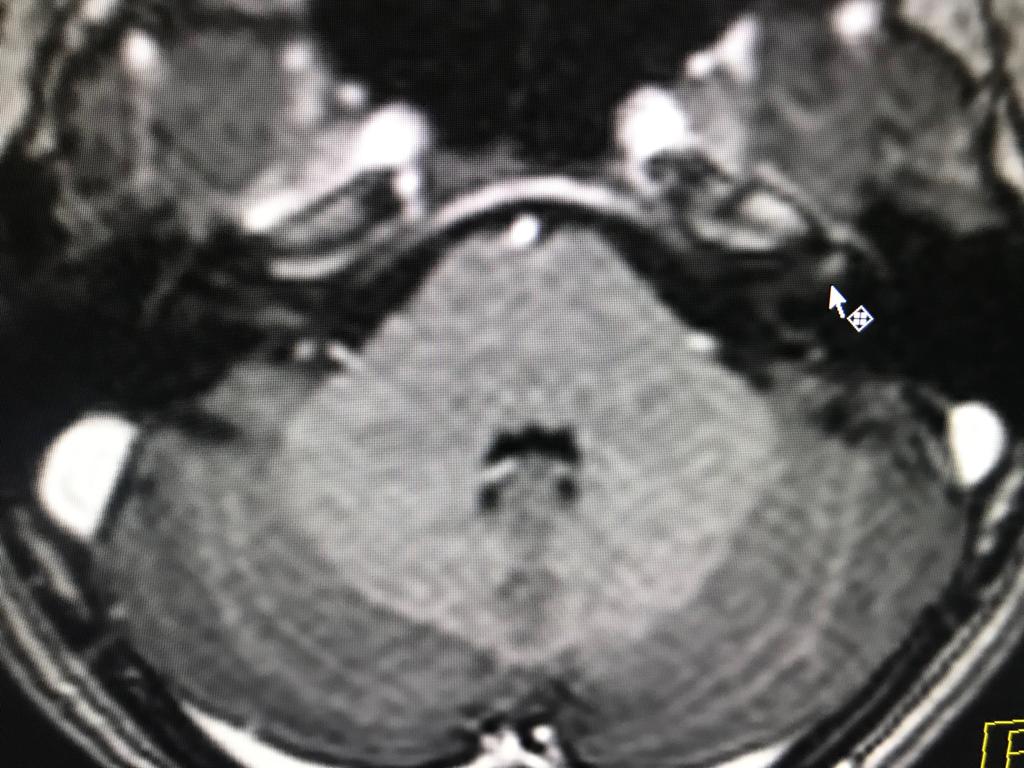

Caso: Neuritis del nervio facial izquierdo. RM cerebral.

Dra. Sterling Arróliga Selva

Lic Francisco Paseta.

Ing Lesther Lira.